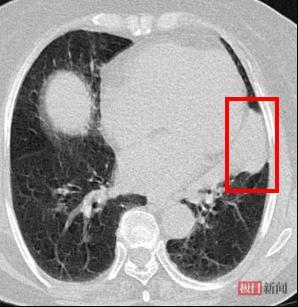

患者术前胸部CT

72岁的赵婆婆患有严重的心脏病,曾植入3个冠脉支架,还伴随有肾功能不全、慢性阻塞性肺疾病、肺气肿和间质性肺炎等。近期,赵婆婆因为长期胸闷去医院检查,发现左上肺有一个肿瘤,并最终通过支气管镜活检确诊为局部晚期的肺鳞状细胞癌。传统的手术切除风险极高,脆弱的心肺肾功能又无法承受全身静脉化疗,赵婆婆和家属心急如焚,多方打听后,慕名来到湖北省中医院(湖北中医药大学附属医院)胸心外科。